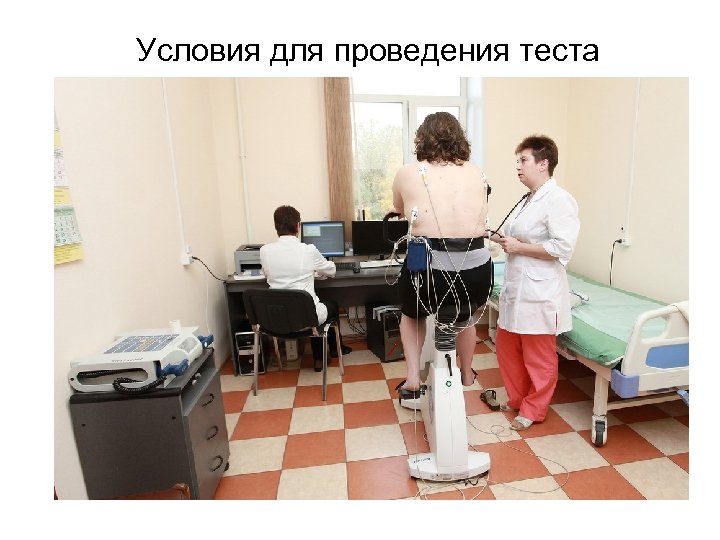

Условия для проведения теста

Условия для проведения теста

Когда проводить тестирование • В первой половине дня • Через 1 -2 часа после легкого завтрака • • Не рекомендуется после забора крови из вены За 2 -3 ч до тестирования нельзя курить

Когда проводить тестирование • В первой половине дня • Через 1 -2 часа после легкого завтрака • • Не рекомендуется после забора крови из вены За 2 -3 ч до тестирования нельзя курить